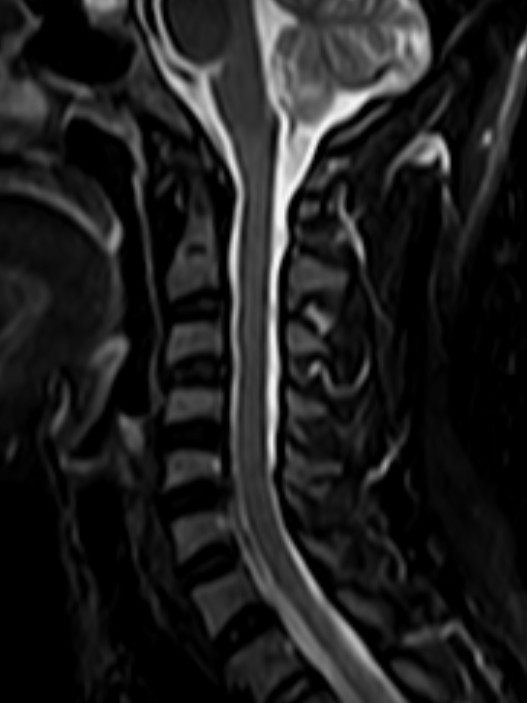

颈椎-T2